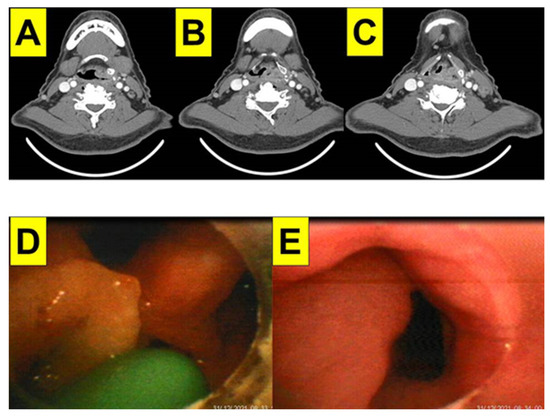

2.1. Case 1: Giant Cemento-Ossifying Fibroma